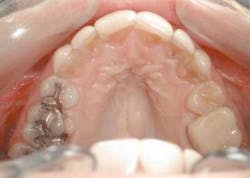

With our patient, this evaluation reveals the centrals to be approximately 8.5 mm wide and 9.5 mm long. (Fig. 3) This would make the existing W/L ratio 89 percent. The Golden Proportion evaluation shows that the centrals appear too wide and we see too much of the canines.

Upon anesthetizing the patient, I decided to remove the old veneers to observe the underlying teeth. I was able to observe the old preparations and the actual color of the teeth. This information will help me with my new preparations (Fig. 6).

We found some severely tetracycline-stained teeth that had hardly any preparation. The result was thick teeth (Fig. 7). This is the main reason the ceramist was not able to correct many of the nuances of the smile design we discussed earlier. Adequate preparation is the only way to obtain a fantastic result.